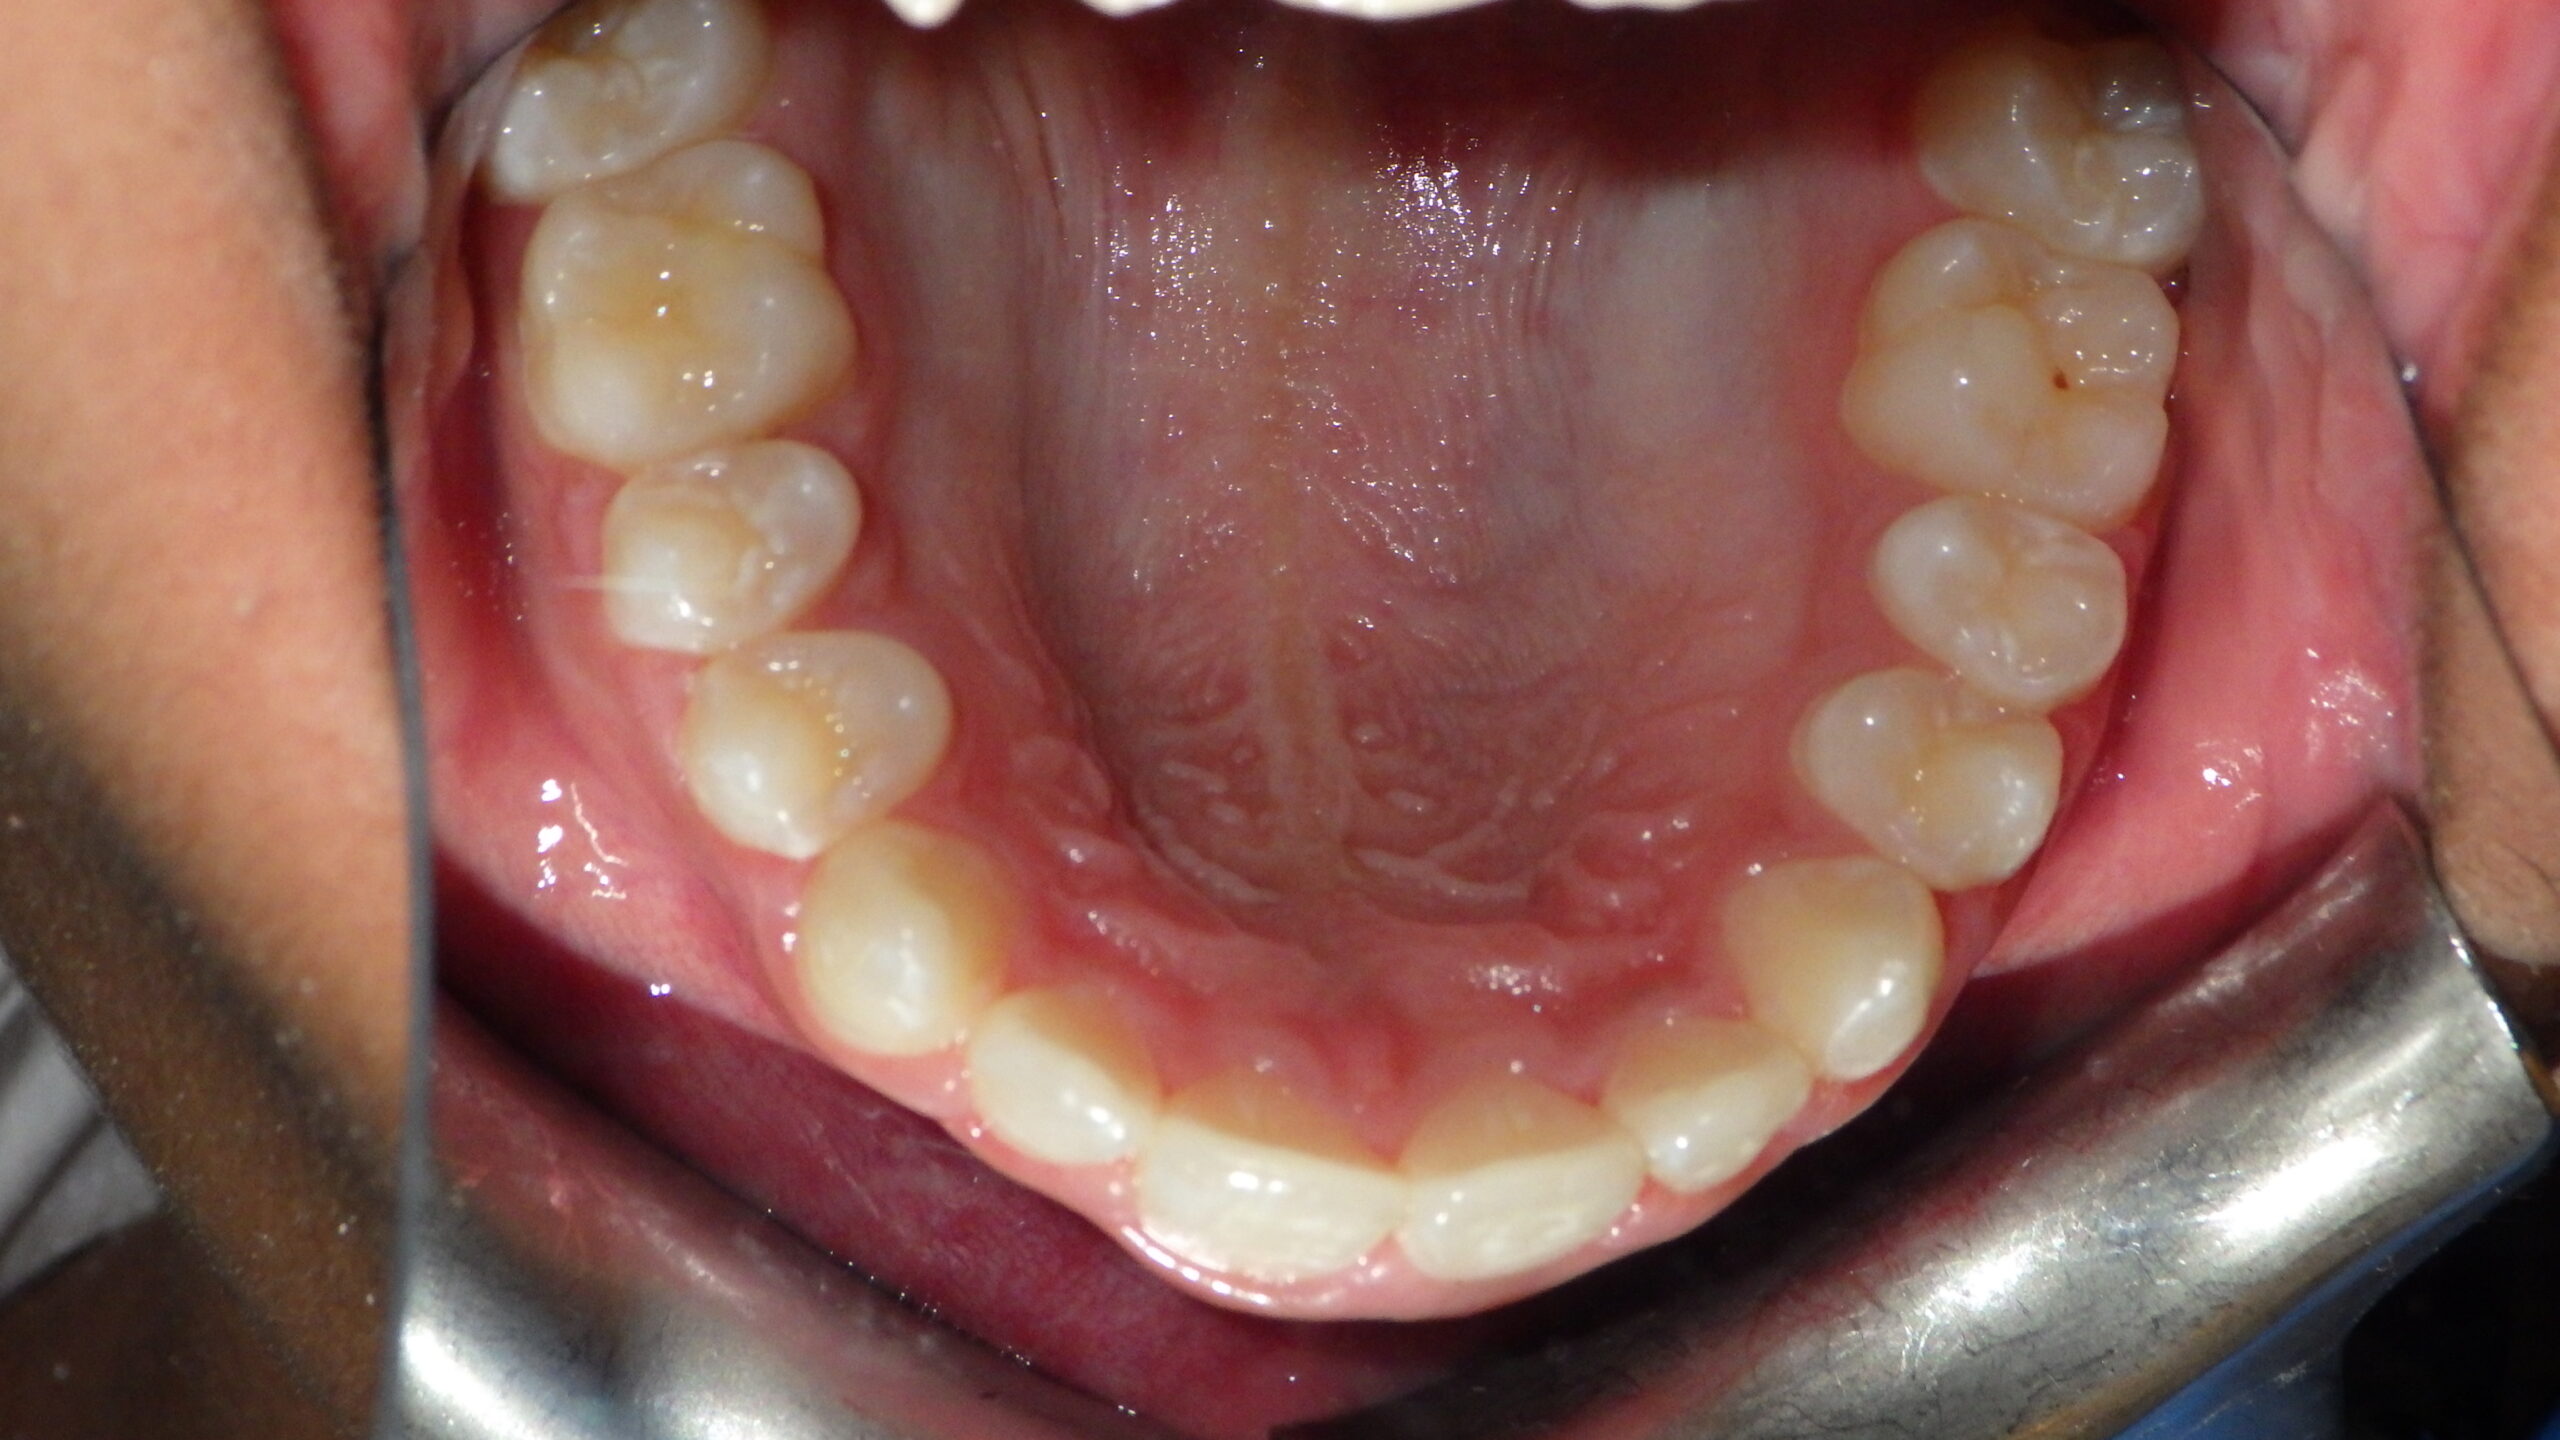

Patient Resultsنتائج المرضى

Real Results. Real Patients.نتائج حقيقية. مرضى حقيقيون.